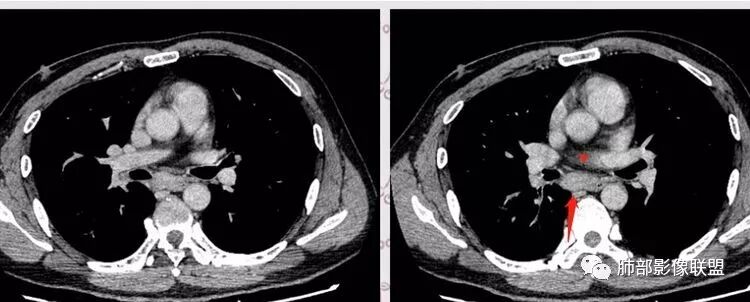

复查胸部CT视频显示肺部病灶明显吸收,淋巴结较前缩小。

患者在本院做了支气管镜,报告是有新生物,取了活检就转院了。病理结果是后来出来的。去肿瘤医院再做支气管镜,病理还是炎症。抗炎治疗(电话追问患者家属,具体不详)一个月后复查,右下肺病变基本吸收,肺门肿块明显变小;纵隔淋巴结基本都没了或者明显变小了

现在看树雾,支原体有可能。只是淋巴结肿大和体重减低有迷惑性

我一直以为是二元的,我觉得特别淋巴结里面又有钙化灶,我的想法肺部就是炎性病变,因为很典型的分布符合气道来源炎性病变,但是淋巴结是独立出来的,里面有钙化灶怀疑结核可能。

淋巴结同步缩小了,其实挺常见的

如果看片考虑二元论,肺部符合急性炎性病变特点。淋巴结真不好说,一元论还没想通,也有存在特异性的可能,比较少。我就这样分析的,写报告我会写二元,把淋巴结独立出来,把右下肺急性炎症独立出来。

南边:当时看淋巴结该不该一元论?一元论该怎么考虑?因为右下肺病变确实没有恶性特点,所以还是考虑二元论。因为薄层CT确实有点状钙化,当时考虑结核可能性大,淋巴结确实涉及少了。

长沟流月去无声:这个人那么多GGO,可以解释他淋巴结的大